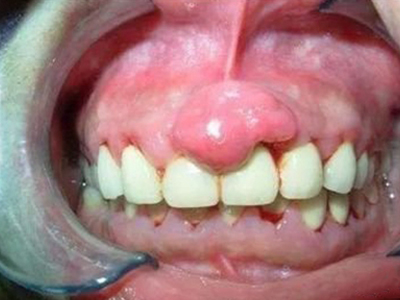

牙龈瘤多发于女性,以青年及中年人为常见,多发生于牙龈乳头部,位于唇、颊侧者较舌、腭侧者多,最常见的部位是前磨牙区。肿块较局限,呈圆形或椭圆形,有时呈分叶状,大小不一,直径由几毫米至数厘米。

肿块有的有蒂,如息肉状;有的无蒂,基底宽广,生长较慢,但在女性妊娠期间可能迅速增大。较大的肿块可以遮盖一部分牙及牙槽突,表面可见牙压痕,易被咬伤而发生溃疡,伴发感染。随着肿块的增长,牙槽骨壁逐渐被破坏,牙可能发生松动、移位。

局部刺激因素,包括菌斑、牙石、食物嵌塞或不良修复体的刺激,引起局部长期慢性炎症,致使牙龈结缔组织形成反应性增生物,即牙龈瘤。此外,牙龈瘤可能和内分泌有关,妇女怀孕期间容易发生牙龈瘤,而分娩后会缩小或停止生长。